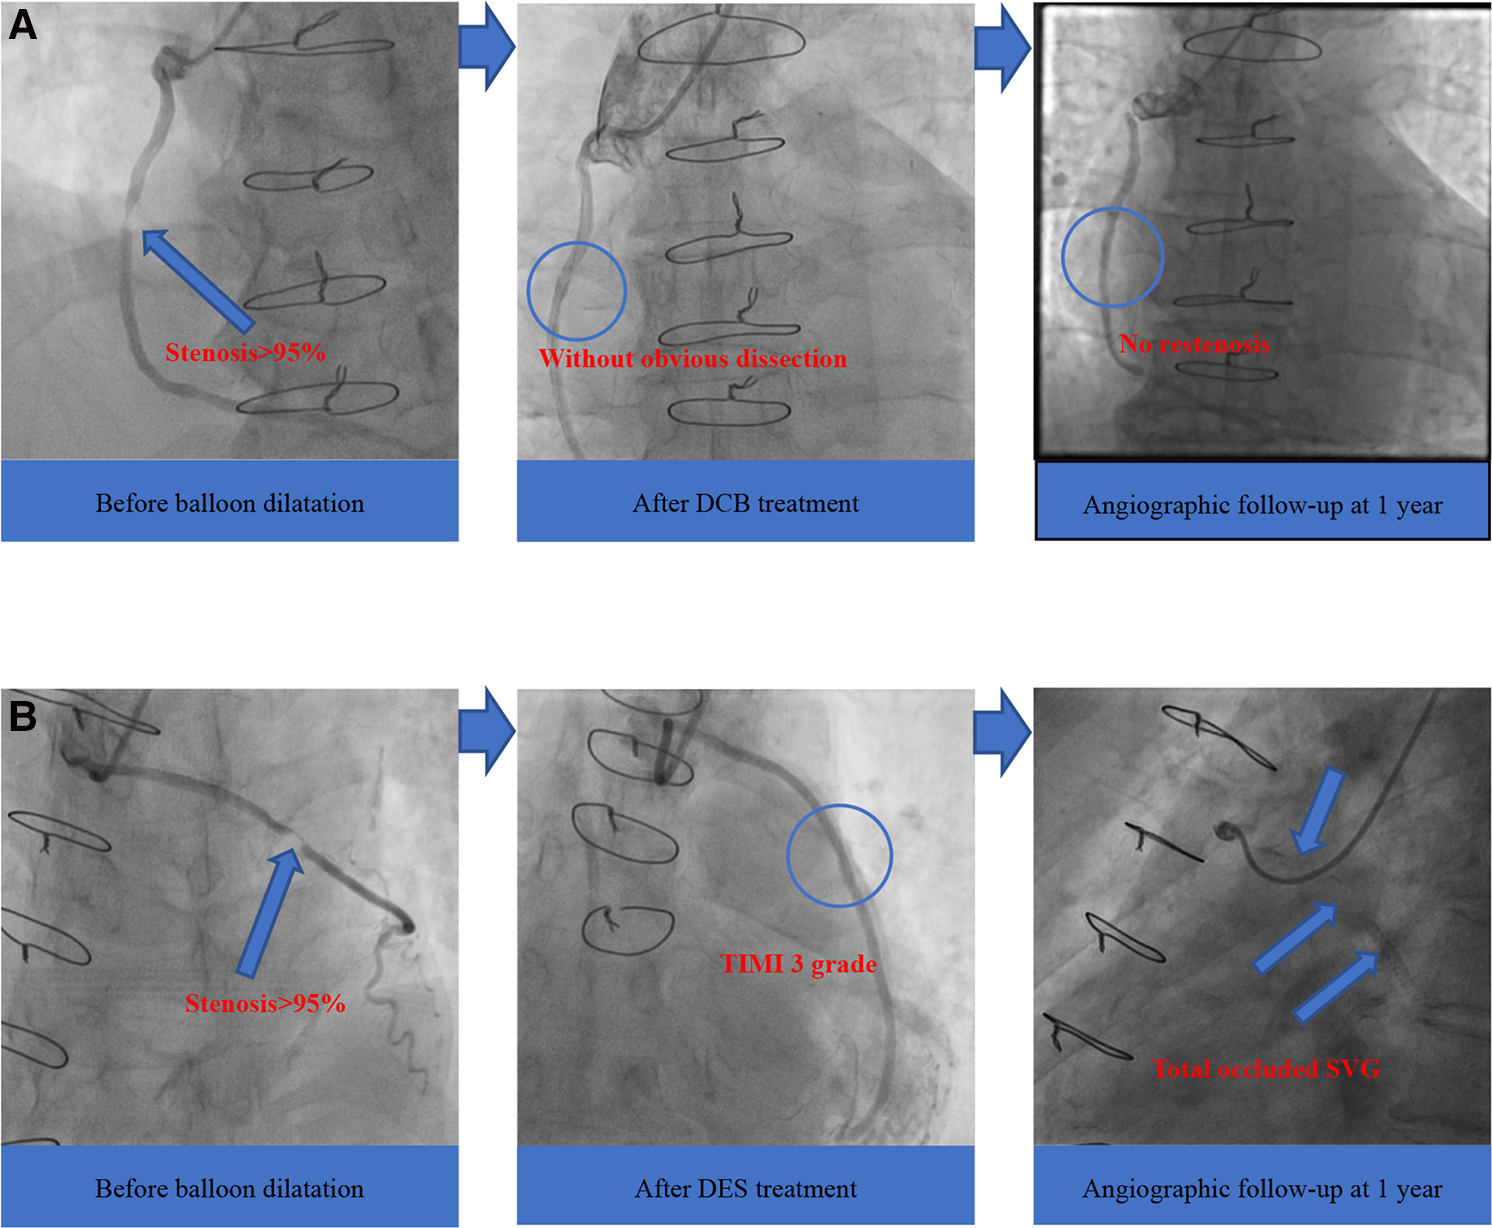

Moreover, we found no occluded SVG after the DCB treatment. In contrast, four patients (17.4%) in the DES group were identified with target vessel occlusion during clinical follow-up (mean follow-up period of 23.0 months), similar to reports from previous research (7). The four total occluded SVG patients in the DES group failed to repeat PCI in the occluded graft and received conservative drug therapy finally, and these four patients did not undergo revascularization procedure of either the SVG or the native coronary artery after index SVG-PCI. An increasing number of randomized controlled trials have utilized DES as a new method for SVG-PCI, but there was no strong evidence for its use (25). Furthermore, DCB, which represents the “leaving nothing behind” strategy, showed encouraging clinical and angiographic results compared with DES (Figure 2). Therefore, we predict that the use of DCB would be a promising trend in the future.

Figure 2

Angiographic outcomes of two groups. (A) DCB group; (B) DES group. DCB, drug-coated balloon; DES, drug-eluting stent; SVG, saphenous vein graft; TIMI, thrombolysis in myocardial infarction.